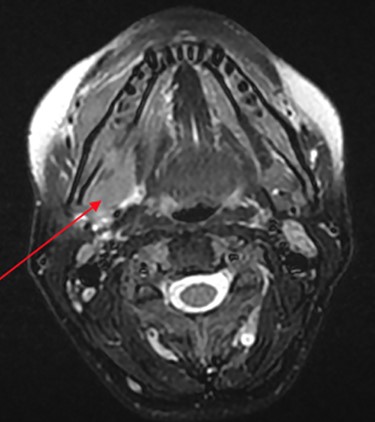

At her OMFS appointment, the consultant was concerned by the abnormal appearance of the extraction site intraorally, combined with the evolving systemic symptoms (Figs 2–4). Urgent magnetic resonance imaging (MRI) head and neck (Figs 5 and 6) and computerized topography (CT) mandible scans were requested and completed in an extremely short time frame.

MRI head (axial view) showing Burkitt’s infiltrating the mandible and oral mucosa.

On the way to this scan, the patient experienced unilateral foot drop and was unable to walk. The scans revealed multifocal neoplastic deposits throughout the jaw, skull base, cervical spine and thyroid. These results, along with suspected malignant spinal cord compression (MSCC), prompted immediate admission to the head and neck ward at Royal Derby Hospital (RDH).